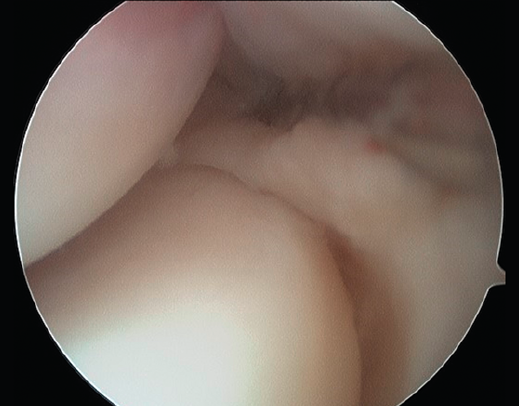

Plica sinovial

La presencia de una plica sinovial radiocapitelar patológica es una fuente potencial de dolor en la cara lateral del codo(31,32). Normalmente pueden existir plicas o pliegues de sinovial como remanente del desarrollo embrionario normal de la membrana sinovial(33). Estas plicas no tienen una función conocida y normalmente no causan ningún síntoma(34), excepto cuando el tejido se hipertrofia tras un traumatismo o por actividades repetitivas, produciendo roce en la articulación radiocapitelar durante el movimiento (Figura 11).

Figura 11. Imagen artroscópica de un codo derecho desde el portal anteromedial. Se aprecia una plica posterolateral.

Para el diagnóstico diferencial con la tendinopatía lateral de codo, la exploración física típica será la que nos haga sospechar esta entidad, acompañada de algunos hallazgos en las pruebas de imagen.

Los principales síntomas diferenciales son dolor selectivo a la palpación en el soft point (el centro del triángulo formado por la cabeza del radio, el epicóndilo y la punta del olécranon) y en la parte posterior de la articulación radiocapitelar; además, puede asociar déficit de extensión, dolor posterolateral durante el final de la extensión y con la pronación-flexión. Los pacientes también pueden describir sensación de tirantez o resalte con la movilidad. Realizar un test de flexión-pronación (donde el examinador realiza flexión pasiva del codo pronado) puede reproducir un chasquido(32).